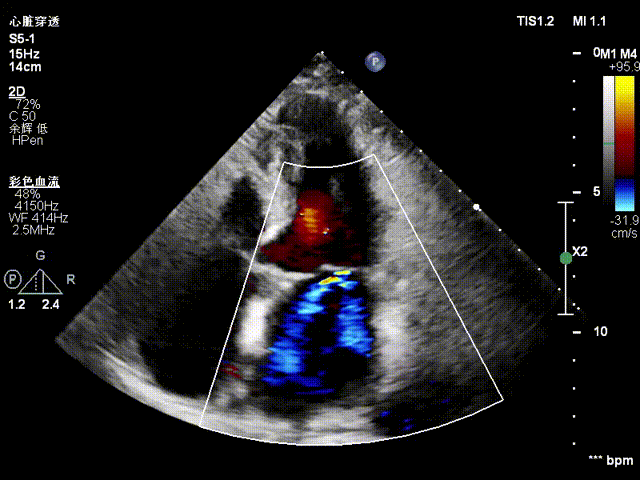

Preoperative precise assessment by transthoracic and transesophageal echocardiography (TTE/TEE) revealed:

Mitral valve: severe functional regurgitation (4+), effective regurgitant orifice area (EROA) 0.52 cm², regurgitant volume 68 mL.

Tricuspid valve: Type IIIb quadricuspid malformation with insufficiency, secondary severe regurgitation (4+), mild annular dilatation (mean diameter 40 mm), mean vena contracta 10 mm. Regurgitant orifices are located at anteroseptal, central, and posteroseptal regions, with marked enlargement of the right atrium and right ventricle.

Mitral Valve Repair Stage: Via the transfemoral venous approach, a 4.0 cm atrial septal puncture was performed, and one mitral valve clip was selected. The unique feature of wide-angle deployment effectively resolved the issue of excessive leaflet tension during valve clip closure. Under the precise guidance of ultrasound, one clip was successfully implanted at the site of the widest regurgitation in the A2-P2 segment of the mitral valve. Immediate postoperative TEE assessment showed that mitral regurgitation was reduced to trivial (1+), the mean transvalvular pressure gradient was only 3 mmHg, and pulmonary venous retrograde flow was significantly improved.

Preoperative Imaging

Mitral regurgitation

3D color Doppler

Mitral valve Zone 2

Color Doppler of Mitral valve Zone 2